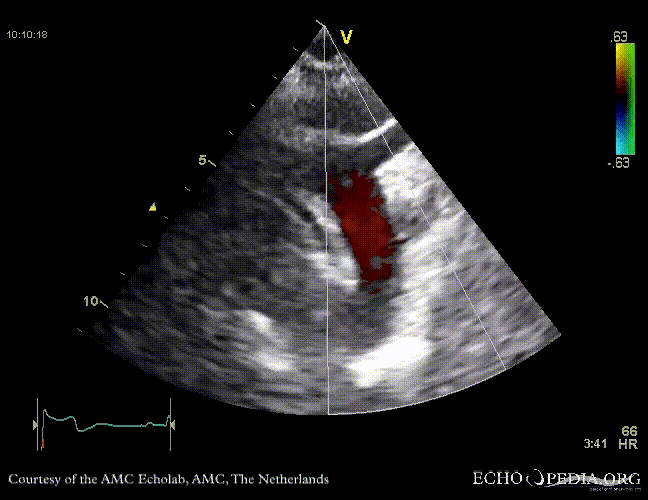

Case 10